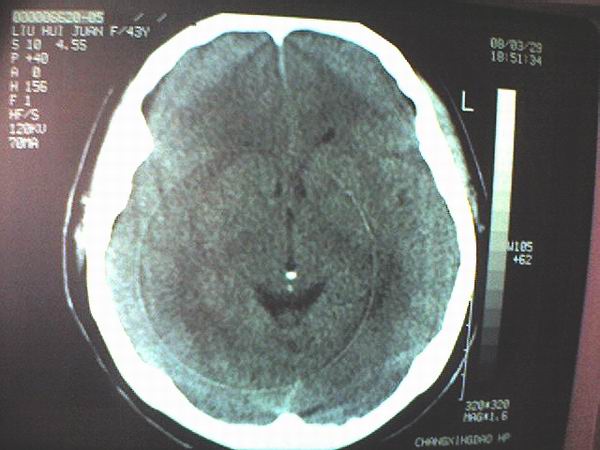

女 43岁 头痛恶心呕吐两天

手机照的,不是太清楚。

右侧大脑镰硬膜下出血

1、右侧大脑镰硬膜下出血2、机器伪影太重,该修修。